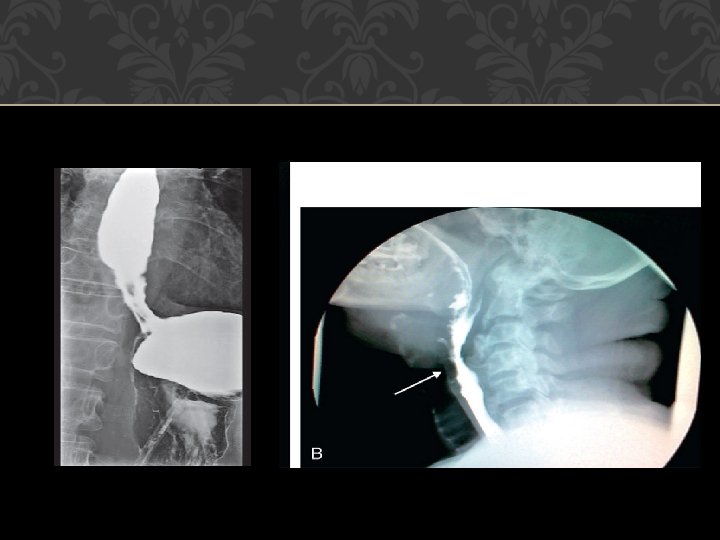

Barium swallow: For malignancy, cardiac achalasia, strictures, diverticulum, hiatus hernia or esophageal spasms. � Cineradiography: For motility disorders of esophageal wall or sphincters. �Ultrasound : Transesophageal echosonography can evaluate the depth of malignant ulcer, which helps in staging the disease.

NORMAL BARIUM SWALLOW